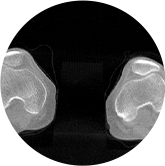

填补常规CT/MR空白

助力术前规划和术后评估

髋关节

膝关节

FOV 250mm

FOV 350mm